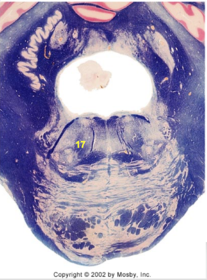

| Head of caudate | |

| Anterior commissure | |

| Thalamus | |

| Substantia nigra | |

| Optic tract | |

| Dentate nucleus | |

| Pons | |

| Longitudinal pontine fibers | |

| Uncus | |

| Superior cerebellar peduncle | |

| Red nucleus | |

| Corticospinal tract (dark) | |

| Pontine nuclei (pale) | |

| Transverse pontine fibers (dark) | |

| Inferior olive | |

| CTT | |

| Medial lemniscus | |

| Nucleus cuneatus | |

| Superior colliculus | |

| Inferior colliculus | |

| Optic nerve | |

| Cerebellum | |

| 4th ventricle | |